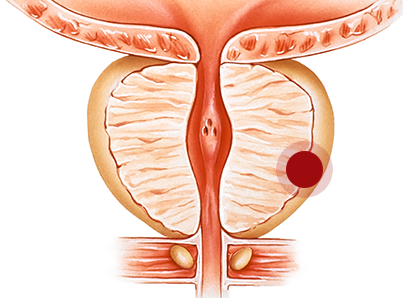

전립선염은 남성 비뇨생식기 질환의 약 25%를 차지하며 남성에게는 빈번하게 발생하는 비뇨기과 질환입니다. 전립선염은 원인도 다양하고 재발이 잦아 보다 확실한 초기 치료가 중요합니다. 만성적인 증상을 호소하는 경우에는 통증, 배뇨 이상 증상을 동반하기 때문에 삶의 질을 떨어질 수 있습니다.

전립선염은 발생 과정의 급성과 만성, 세균 감염 여부, 염증 유무, 증상의 유무에 따라 분류를 하게 되며 원인에 올바른 치료 방법을 선택해야 합니다.

요도나 직장 직접 전파 및 림프관을 통해 세균에 감염된 경우

요도나 직장 직접 전파 및 림프관을 통해 세균에 감염된 경우 세균으로 혈액성 감염이 된 경우

세균으로 혈액성 감염이 된 경우 성관계를 통해 감염된 경우

성관계를 통해 감염된 경우 요도괄약근에 이상으로 인한 요역류

요도괄약근에 이상으로 인한 요역류 전립선 주위 정맥의 순환 장애

전립선 주위 정맥의 순환 장애